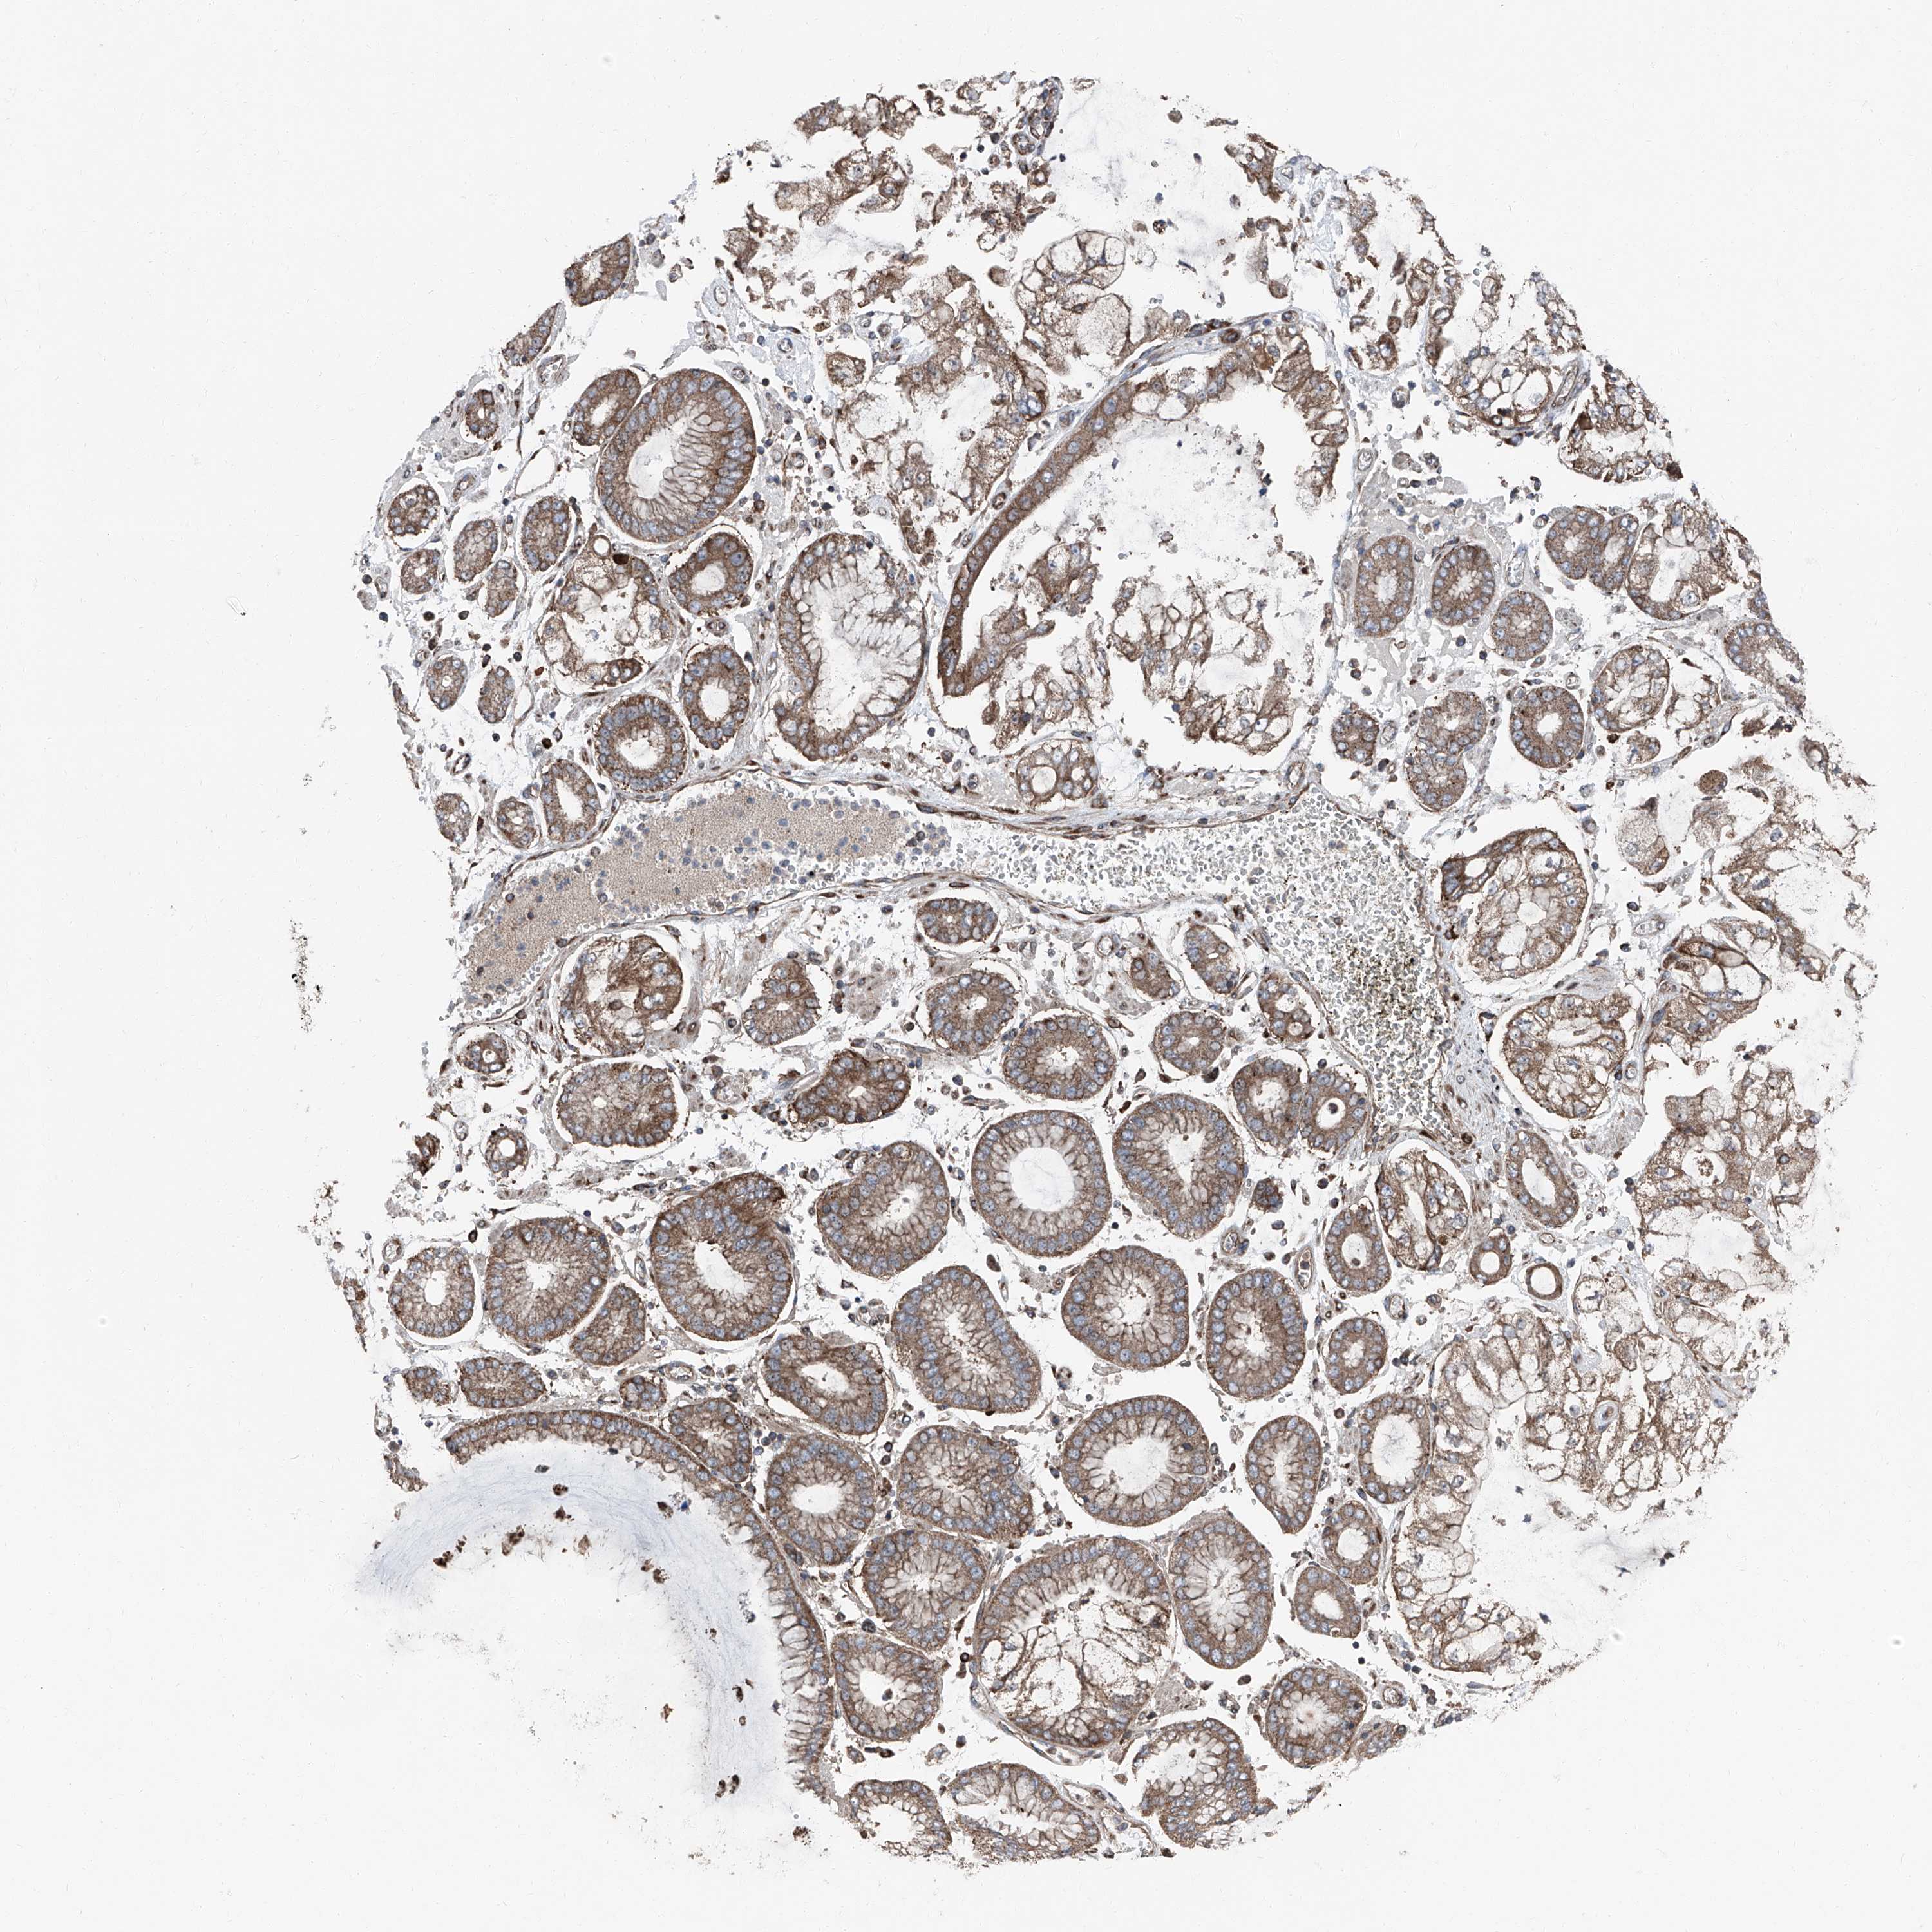

STOMACH CANCER - Protein expressioni

A mouse-over function shows sample information and annotation data. Click on an image to view it in a full screen mode. Samples can be filtered based on level of antibody staining by selecting one or several of the following categories: high, medium, low and not detected. The assay and annotation is described here.

Antibody stainingi

Antibody staining in the annotated cell types in the current human tissue is reported as not detected, low, medium, or high, based on conventional immunohistochemistry profiling in selected tissues. This score is based on the combination of the staining intensity and fraction of stained cells.

Each image is clickable and will lead to virtual microscopy that enables deeper exploration of all samples and also displays staining intensity scores, fraction scores and subcellular localization as well as patient and tissue information for each sample.

Antibody HPA028516

Antibody HPA073571

Staining

High

Medium

Low

Not detected

Intensity

Strong

Moderate

Weak

Negative

Quantity

>75%

75%-25%

<25%

None

Location

Nuclear

Cytoplasmic/membranous

Cytoplasmic/membranous,nuclear

Adenocarcinoma, NOS

Adenocarcinoma, High grade